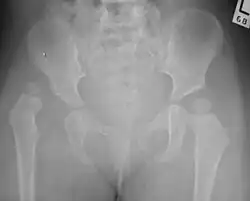

X-Ray Image showing hip dysplasia in a baby